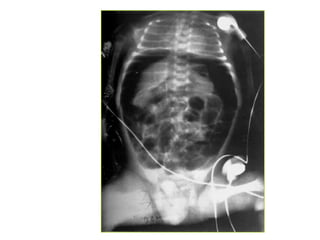

1. Daõn caùc quai ruoät, möïc nöôùc hôi

2. Khí töï do trong oå buïng

3. Khí trong thaønh caùc taïng

*Daáu hieäu: daõn, tröôùng hôi vaø dòch

1. Ruoät non > 3cm

2. Ruoät giaø > 6cm, manh traøng > 8cm

3. Möïc nöôùc – hôi ( xuaát hieän töø 12-24giôø)

4. Thaønh ruoät phuø neà ( >3mm)

5. OÅ buïng môø (dòch trong oå buïng)